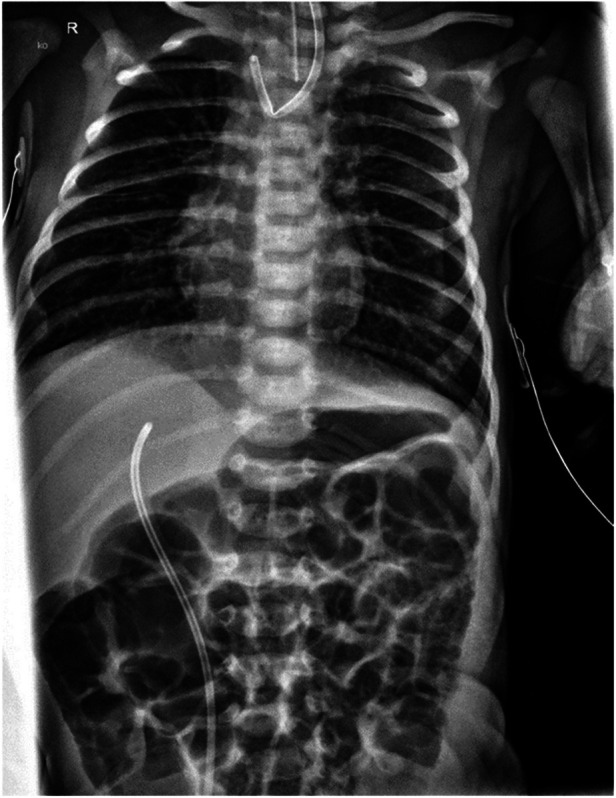

Case report: A term boy (GA: 42 + 1 weeks; BW: 3,110 g) underwent thoracoscopic TEF repair for Type C EA. We ligated the fistula using a polymer clip followed by primary esophageal anastomosis on the second day of life. At ten weeks of age, we readmitted the infant due to recurrent bronchitis and episodes of postprandial coughing. Flexible bronchoscopy revealed that the polymer clip, previously employed for fistula closure, had migrated into the right main bronchus and was subsequently retrieved. Despite clip removal, persistent coughing prompted further evaluation, revealing a recurrent TEF on contrast esophagography. An interdisciplinary team successfully obliterated the recurrent fistula using endoscopic chemocauterization with trichloroacetic acid (TCA) via rigid bronchoscopy. Additionally, due to a developing anastomotic stricture, the patient required four balloon dilations and a single triamcinolone injection. At the three-year follow-up, the patient is eating well and thriving normally.